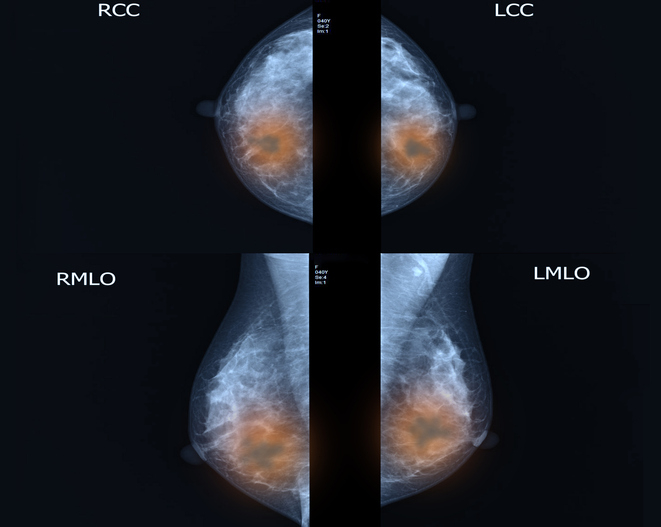

한 달에 한 번씩 자가검진을 실시하면서 병원에서 매년 정기검진을 받아, 의심 증상이 있으면 추가 검사에 나서야 한다. 병원에서 받는 유방암 기본 검사는 유방 엑스레이(유방촬영술), 유방초음파 등이 있다. 이 센터장은 "한국 여성은 유선조직이 풍부한 치밀유방이 많아 유방 초음파검사가 유방암 진단의 기본 검사"라며 "국가건강검진 40세 이상 여성 암 검사에 포함되는 유방촬영술은 미세석회화, 구조 왜곡 관찰에 용이해 두 검사는 상호보완 검사"라고 설명했다.

유방초음파와 유방촬영술은 서로 보완하는 성격을 띠므로 전문의와 상담해 1년에 한 번씩은 적절한 검사를 시행하는 게 권장된다. 임산부나 수유 중인 여성도 시기를 놓치지 말고 초음파검사를 받는 게 추천된다.